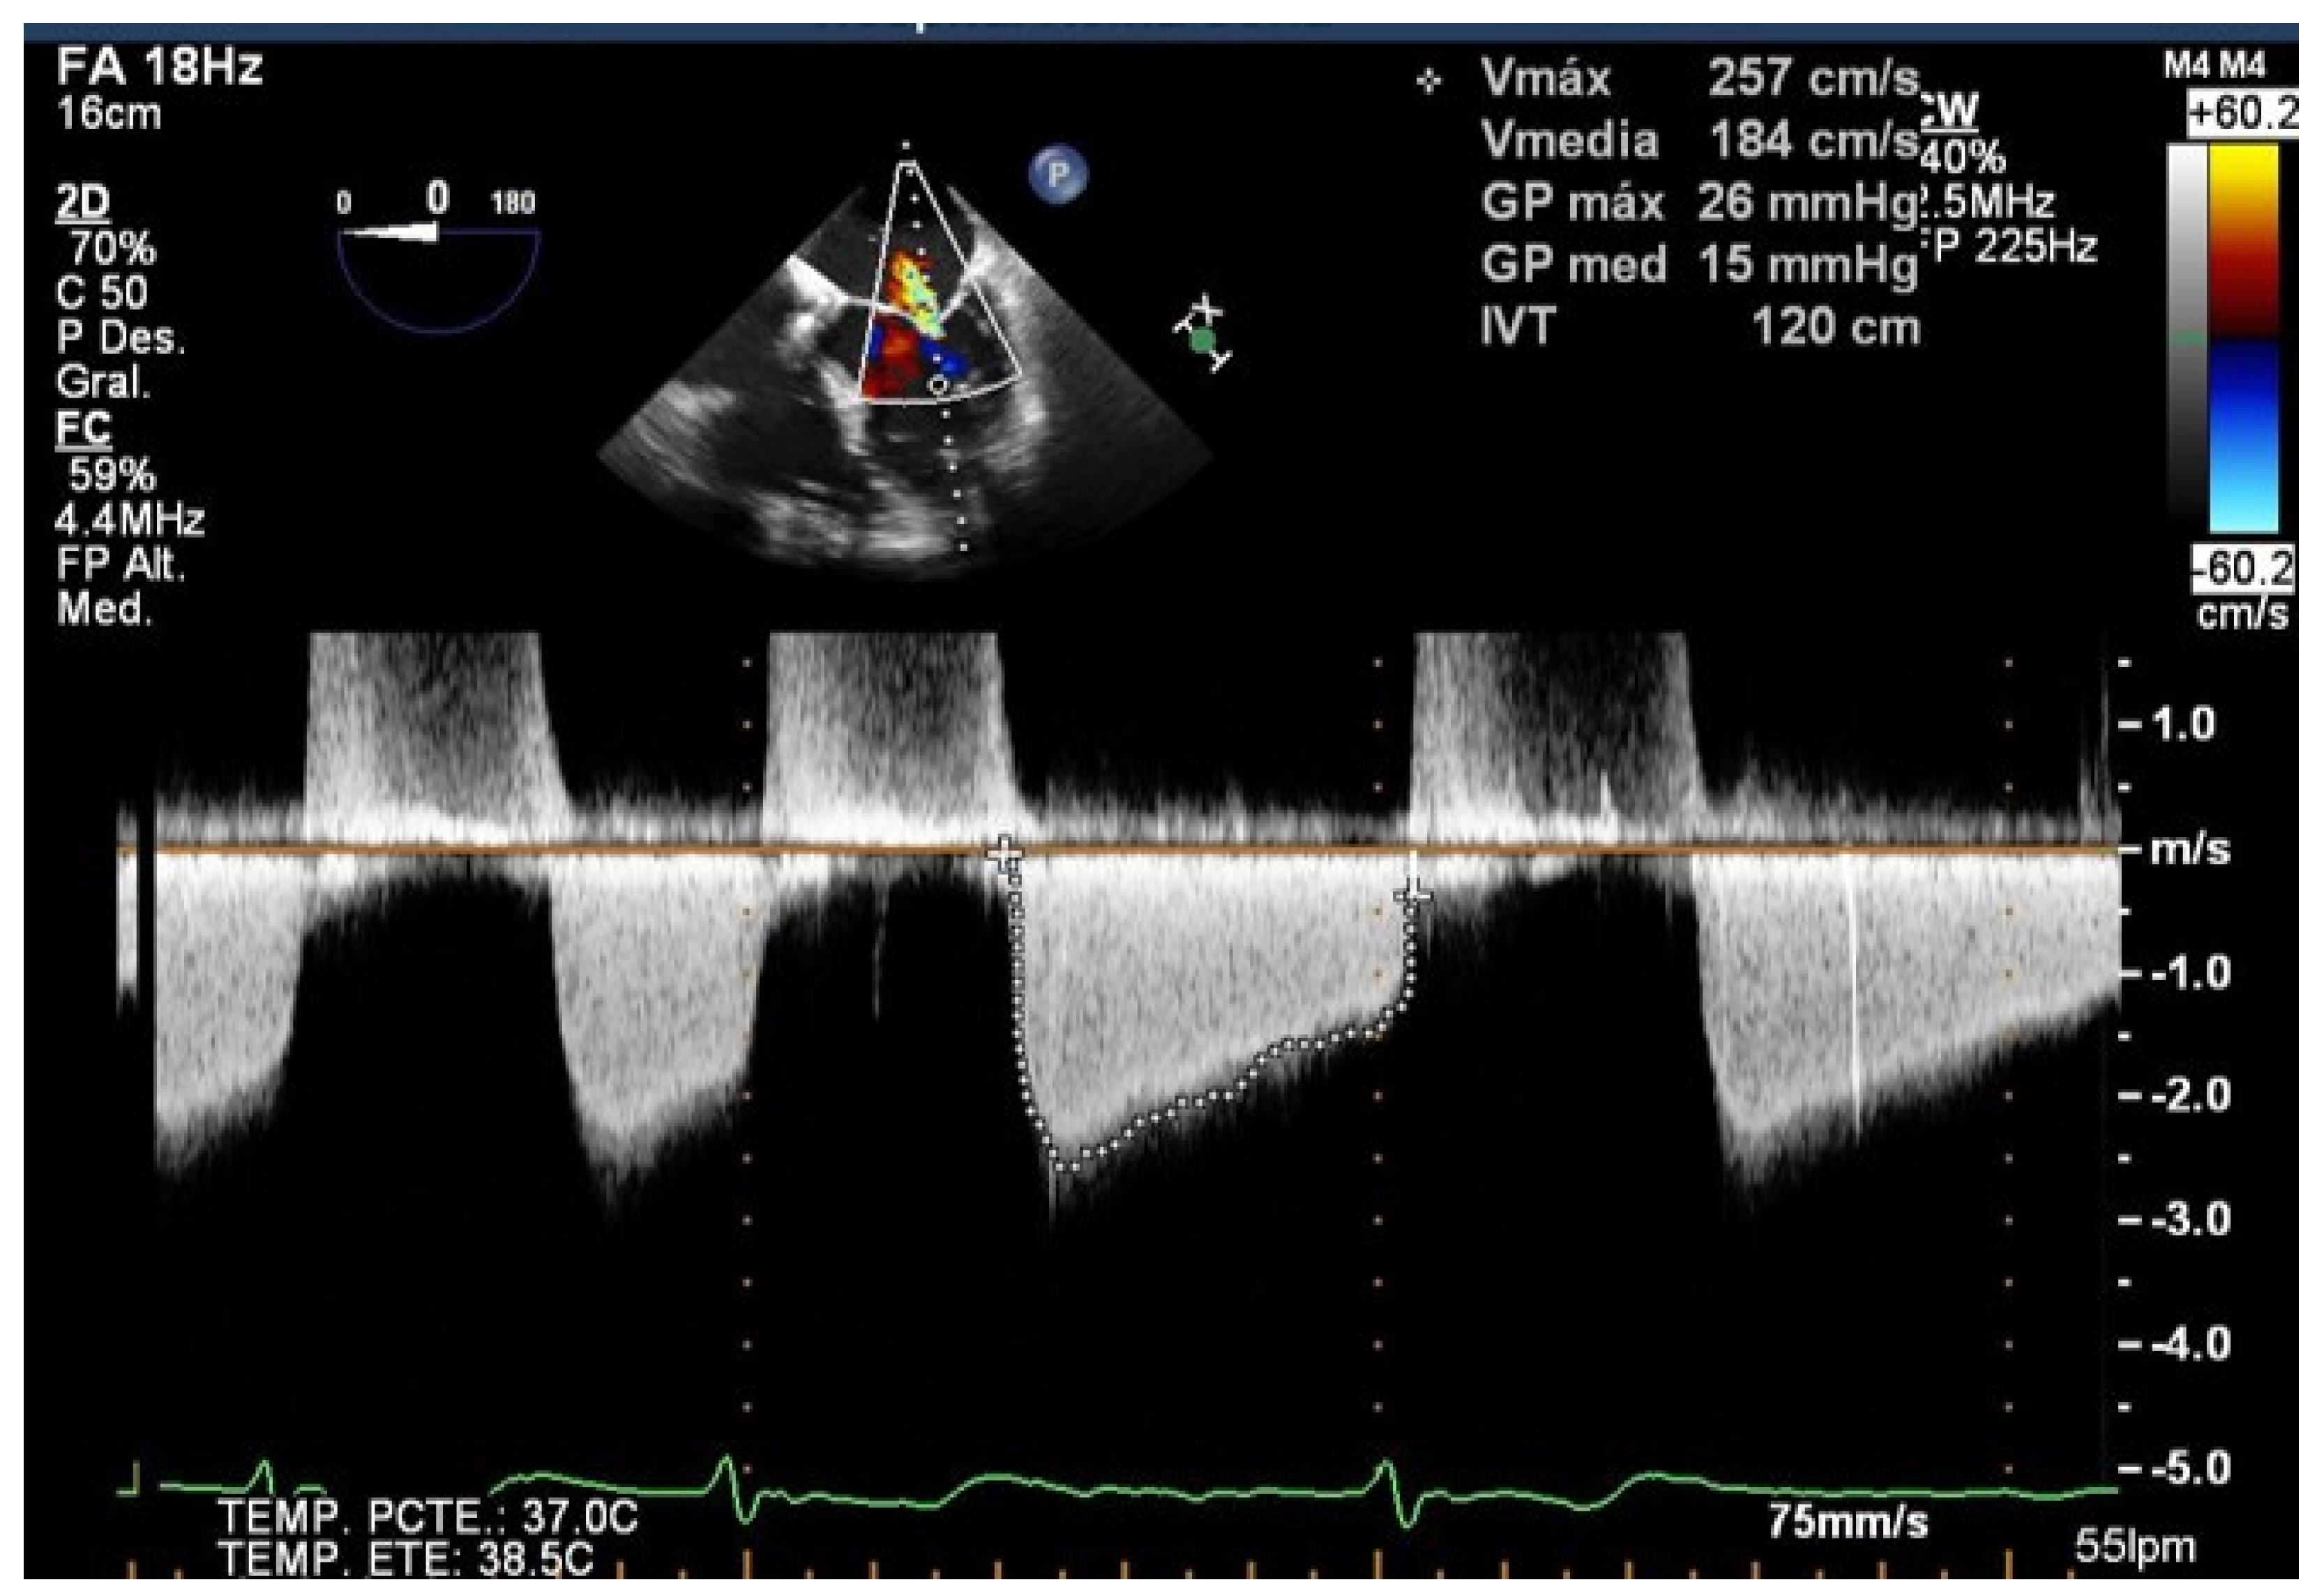

Figure 3.

Severe mitral stenosis after implantation of a mitral clip measured by Doppler echo.

TEE allows us to study the basal mitral area (which must be at least more than 4 cm2), and the mobility, flexibility, and thickness of the leaflets in order to avoid significant mitral stenosis when one or more clips are implanted. Likewise, TEE is essential in the evaluation of the appearance of mitral stenosis after grasping. Medium gradients greater than 5 mmHg are not acceptable since they have been related to worse outcomes [19] (Figure 3). When this happens, the grasping must be carried out again to try to avoid the stenosis, and the implant must be abandoned when this is not possible.